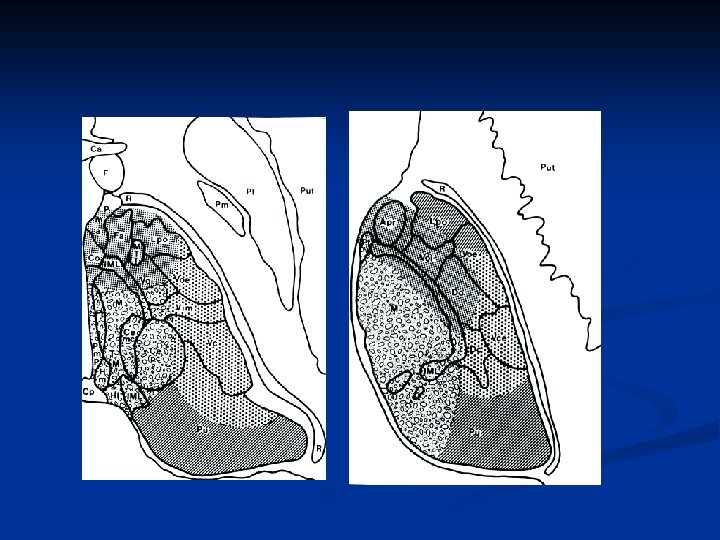

Anatomy of anterior thalamic nucleus n Blood supply Tuberothalamic (Polar) artery form P-com n Afferent *Mammillary body (mammillothalamic tract) *Ventral amygdalofugal fiber (inferior thalamic peduncle) n Efferent cingulate gyrus

Input Nucleus Output Amygdala/perirhinal cortex Inferior temporal cortex Hypothalamus Intralaminar thalamic nucleus dorsomedial thalamus pre-frontal lobes anterior nuclei cingulate gyrus & hippocampus Supplementary motor Anterior insular cortex mamillary bodies. . .

Neuropsychological disturbances of Ant. Thalamic lesion n Disturbances of alertness Intralaminar, reticular, ventral anterior nuclei n Apathy , disinterest, lack of drive for motor expression anterior thalamic nucleus- cingulate gyrus: frontal hypometabolism n Memory disturbance * Mammillothalamic tract * Ventral amygdalofugal fiber (perirhinal cortex) Left : verbal, Right: visuospatial Anterograde, sometimes retrograde, disorientation to time, normal working memory